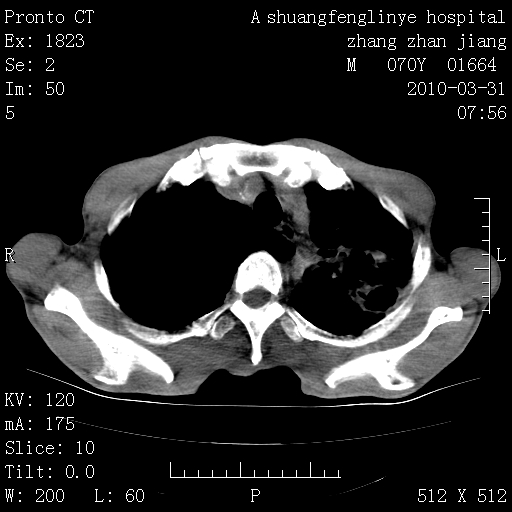

标题: CT25450:肺结核?

双上肺继发型tb并左上空洞形成,主动脉冠脉钙化。

1)两肺上叶继发性肺结核并左肺上叶空洞形成。2)冠状动脉及主动脉钙化。